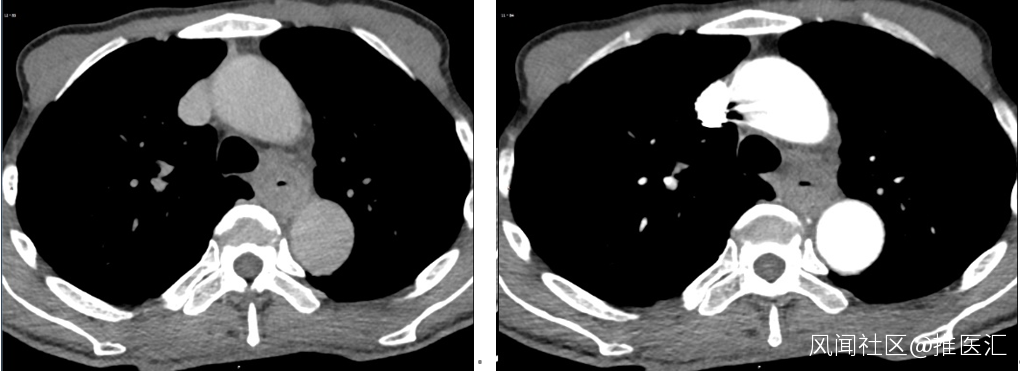

圖1:胸部強化CT圖片;A.靜脈期;B.動脈期

強化CT的結果發現食管佔位,肝臟多發轉移癌。肝臟穿刺活檢的病理結果提示為惡性腫瘤,形態像是小細胞癌,需要做免疫組織化學檢測進一步確定。